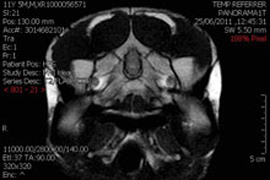

Эпилепсия - хроническое неврологическое заболевание, сопровождающееся судорожными приступами. Причиной приступов являются повреждения мозга, такие как инсульт, опухоли головного мозга, черепно-мозговые травмы (ЧМТ) или поражения центральной нервной системы. К счастью, регулярные осмотры и лечение в большинстве случаев приводят к ремиссии, рассказывает Science World Report.

Ранее эффективных методов, помогающих предсказать, когда случится следующий приступ, не существовало. Исследователь отмечает: созданный им метод позволит спрогнозировать вероятность приступа с точностью в 82%. Алгоритм был разработан благодаря конкурсу, объявленному в августе прошлого года.

Более 500 исследовательских команд со всего мира попытались придумать способ, который позволил бы выявлять и предсказывать приступы. Конкурс выиграл Майкл Хиллз, инженер по вычислительной технике из Австралии. Его алгоритм классифицирует различные аспекты локализованного потенциала электрического поля в головном мозге.